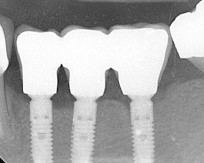

Контрольный снимок — ортопантомограмма: